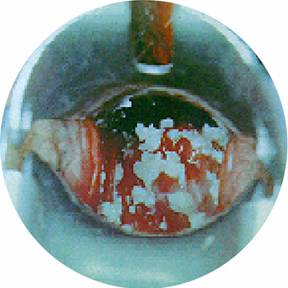

รูปที่ 2 ก้อนเนื้อมะเร็งปากมดลูกของจริงที่ถูกตัดออกมาพร้อมปากมดลูก แน่ใจหรือว่าเป็นตกขาวปกติ? “คงเป็นตกขาวปกติ ไม่มีอะไรหรอก” ที่กล่าวว่าเป็นการอ้างก็เพราะเป็นธรรมดาของหญิงไทยที่มักจะขี้อาย เรียบร้อยเหมือนผ้าพับไว้บ้าง ไม่เหมือนบ้าง แต่ก็มักจะอายกันเป็นส่วนใหญ่ ผิดกับเด็กหญิงอเมริกันที่เริ่มตรวจภายในกันตั้งแต่วัยทีนเอจ แต่ก็เป็นข้อดีไม่น้อยเพราะทำให้อัตราการตายจากโรคมะเร็งปากมดลูกไม่สูงเท่า ในคนไทยเรา เพราะเมื่อตรวจภายในได้ส่องเข้าไปดูถึงปากมดลูก ถ้าเห็นติ่งเห็นก้อนอะไรผิดปกติก็สามารถตัดและแก้ได้ทันตั้งแต่เนิ่นๆ มะเร็งยังไม่ทันลามไปต่อมน้ำเหลืองก็สกัดได้ทันก่อน พอมาเห็นคุณย่าคุณยายบ้านเราที่กว่าจะตรวจพบมะเร็งก็ “สายเสียแล้ว” ถึงรู้สึกเสียใจและเสียดายมากๆทีเดียวครับ